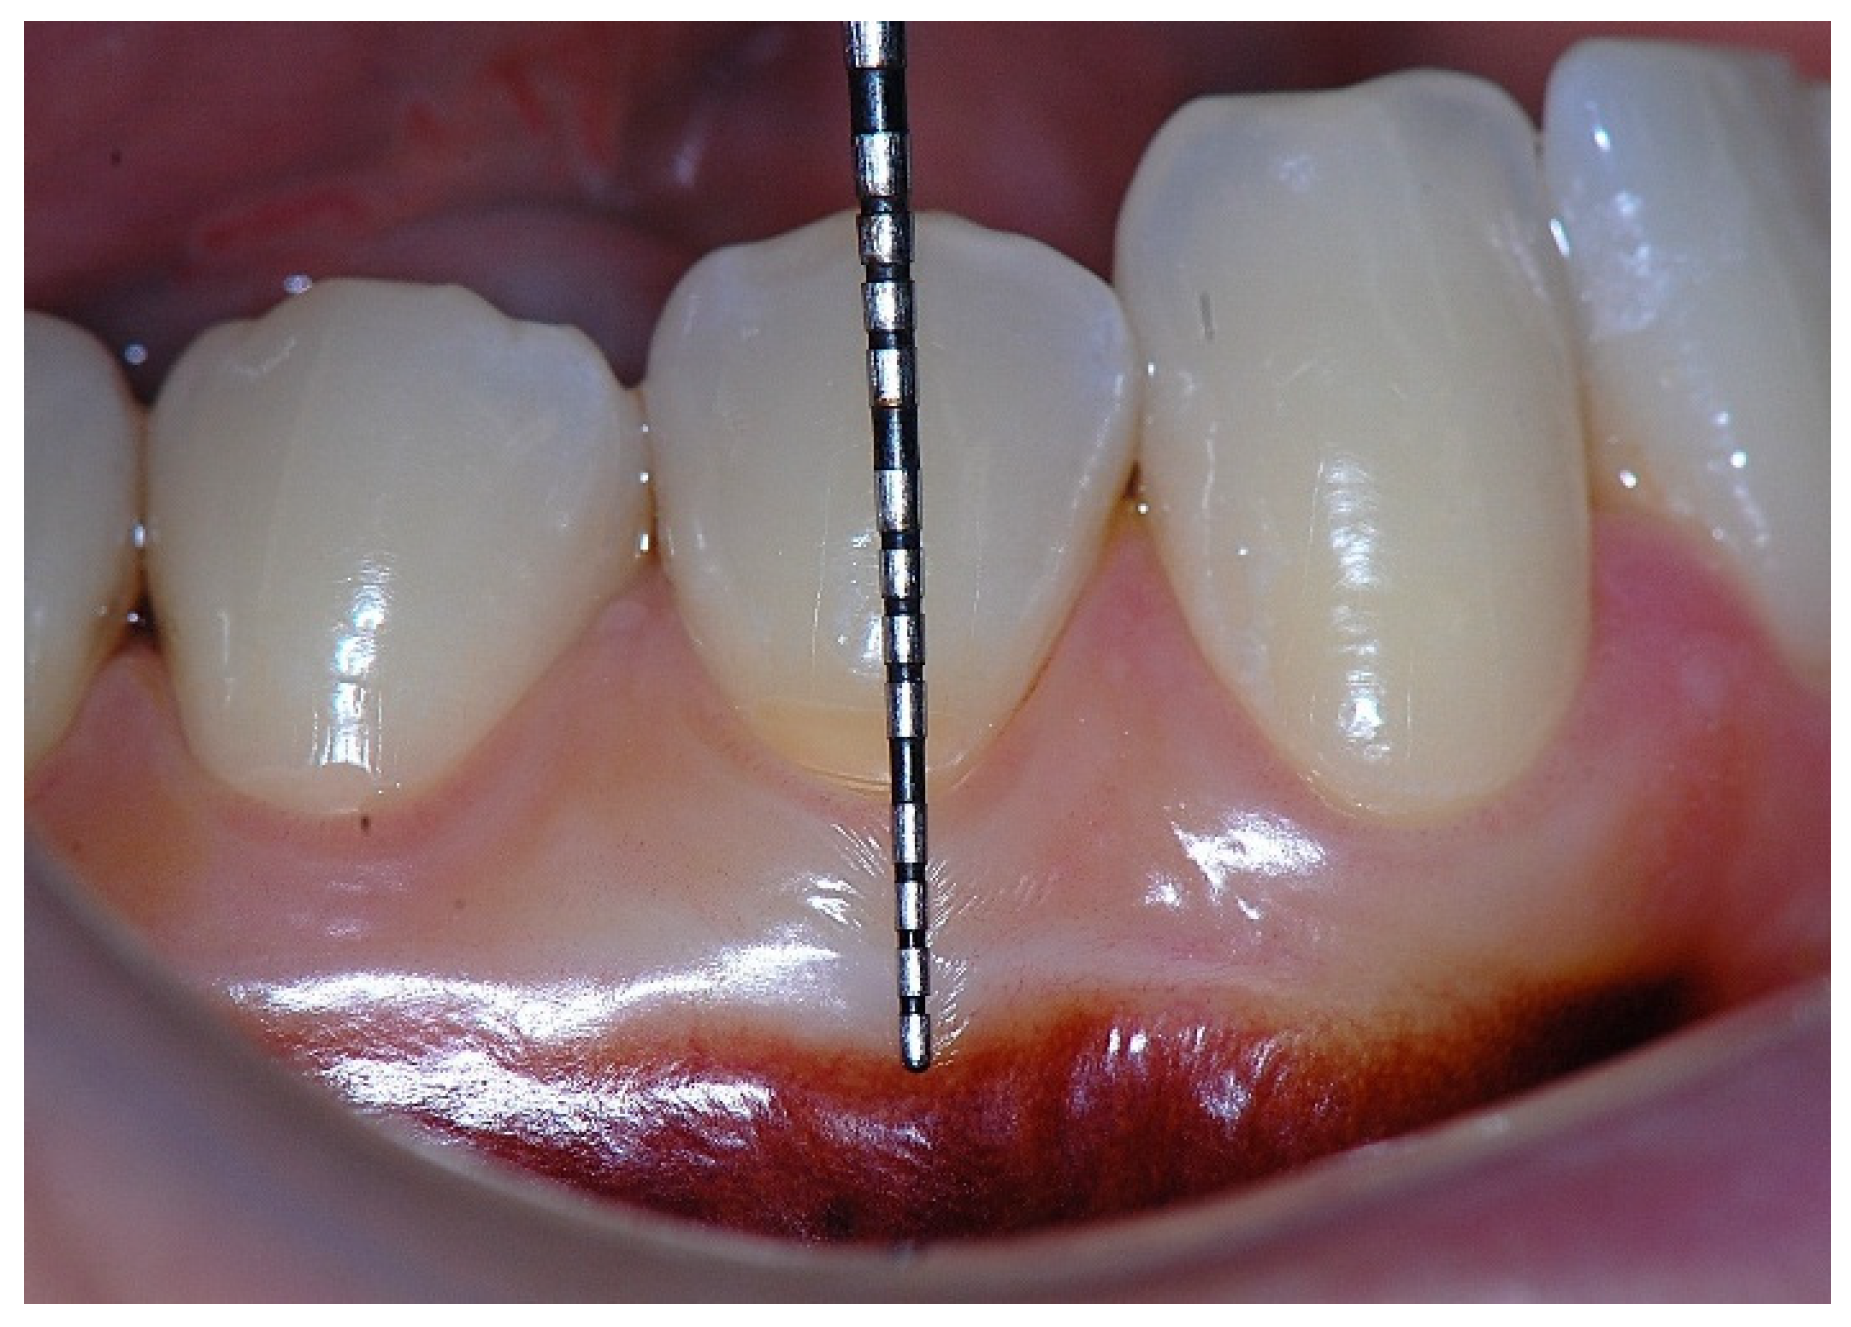

Figure 1. Probing depth of 1 mm is associated with approximately 1 mm of epithelial attachment.

In a clinical scenario characterized by 2 mm of keratinized tissue and a sulcus depth of 1 mm, a stable and mechanically resistant connective tissue attachment is not present [1]. This is attributable to the fact that most connective tissue fibers inserting into the root surface are associated with non-keratinized, mobile mucosal tissues (Figure 1), which are elastic in nature and therefore incapable of stabilizing the gingival margin (Figure 2 and Figure 3). In contrast, when these fibers are embedded within keratinized tissue, they are firmly anchored to both the tooth and alveolar bone and are comparatively immobile, thereby contributing to gingival margin stability (Figure 4, Figure 5 and Figure 6).